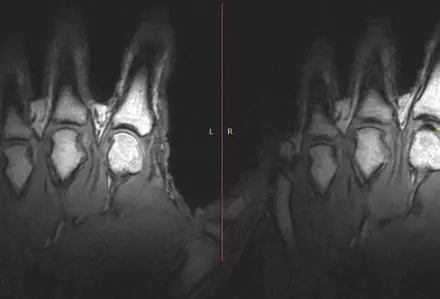

Медики раскрыли тайну хруста суставов Ученые наблюдали за хрустящими пальцами с помощью томографа. © Gregory Kawchuk

Чтобы поставить точку в этом вопросе, канадский специалист Грег Кочук (Greg Kawchuk) и его коллеги провели тщательное исследование "чемпиона по хрусту пальцев" Джерома Фрайера. Помощником ученых выступил современный томограф, способный получать информацию с большим временным разрешением.

Пальцы мужчины помещались в специальные трубки, которые осторожно вытягивали их, пока тот неподвижно лежал в томографе, - и тем самым заставляли хрустеть. Весь процесс разворачивался около 300 миллисекунд и впервые предстал изумленным глазам ученых во всех деталях.

Наблюдения подтвердили первоначальную версию о том, что хруст связан с появлением микропузырьков. Теперь Кочук и его коллеги намерены ответить на следующий животрепещущий вопрос: полезно ли хрустеть суставами?